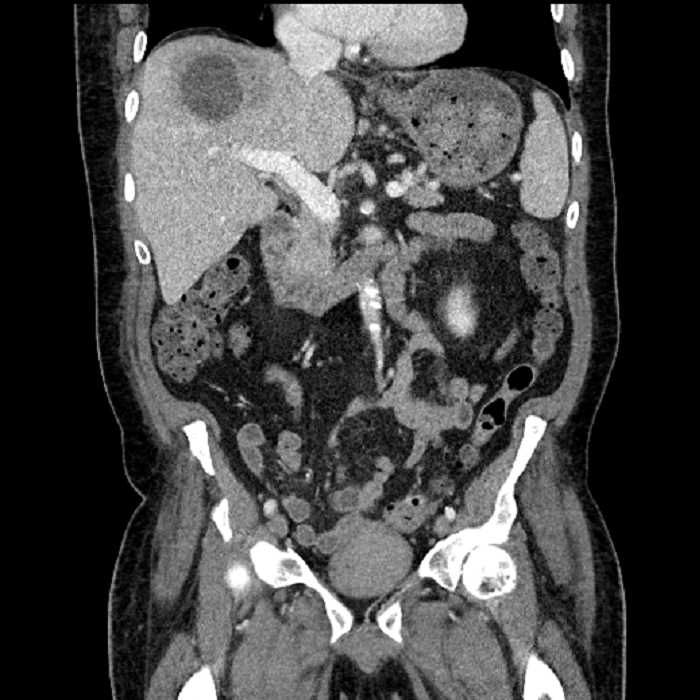

• Large fluid density structure in hepatic segments 7 and 8 measuring 10 x 7 x 7 cm with internal septation and circumferential ill-defined low density compatible with edema

• Peripherally enhancing subcapsular collections along the anterior margin of the left hepatic lobe measuring 3 x 1 cm and 2 x 1 cm

• Clearly marginated fluid density structure in segment 7 and several other scattered tiny hypodensities, which likely represent cysts

Acute sigmoid diverticulitis complicated by a small contained perforation and a large abscess in the right hepatic lobe. Additional small subcapsular abscesses along the anterior margin of the left hepatic lobe.

Additionally, loss of the normal fat plane between the peridiverticular collection and adjacent thickened loops of small bowel raises the potential for an enterocolonic fistula.

• The classic CT imaging appearance is a double target sign with internal low density surrounded by an internal enhancing rim (capsule) and a low density external rim (edema)

Hepatic abscess showing the double target sign with low density internally surrounded by a thin inner enhancing rim (red arrow) and ill-defined outer low density rim (yellow arrow). Blue arrow indicates an internal septation. Red arrows: additional smaller subcapsular abscesses. Red arrow: focal contained perforation associated with diverticulitis.